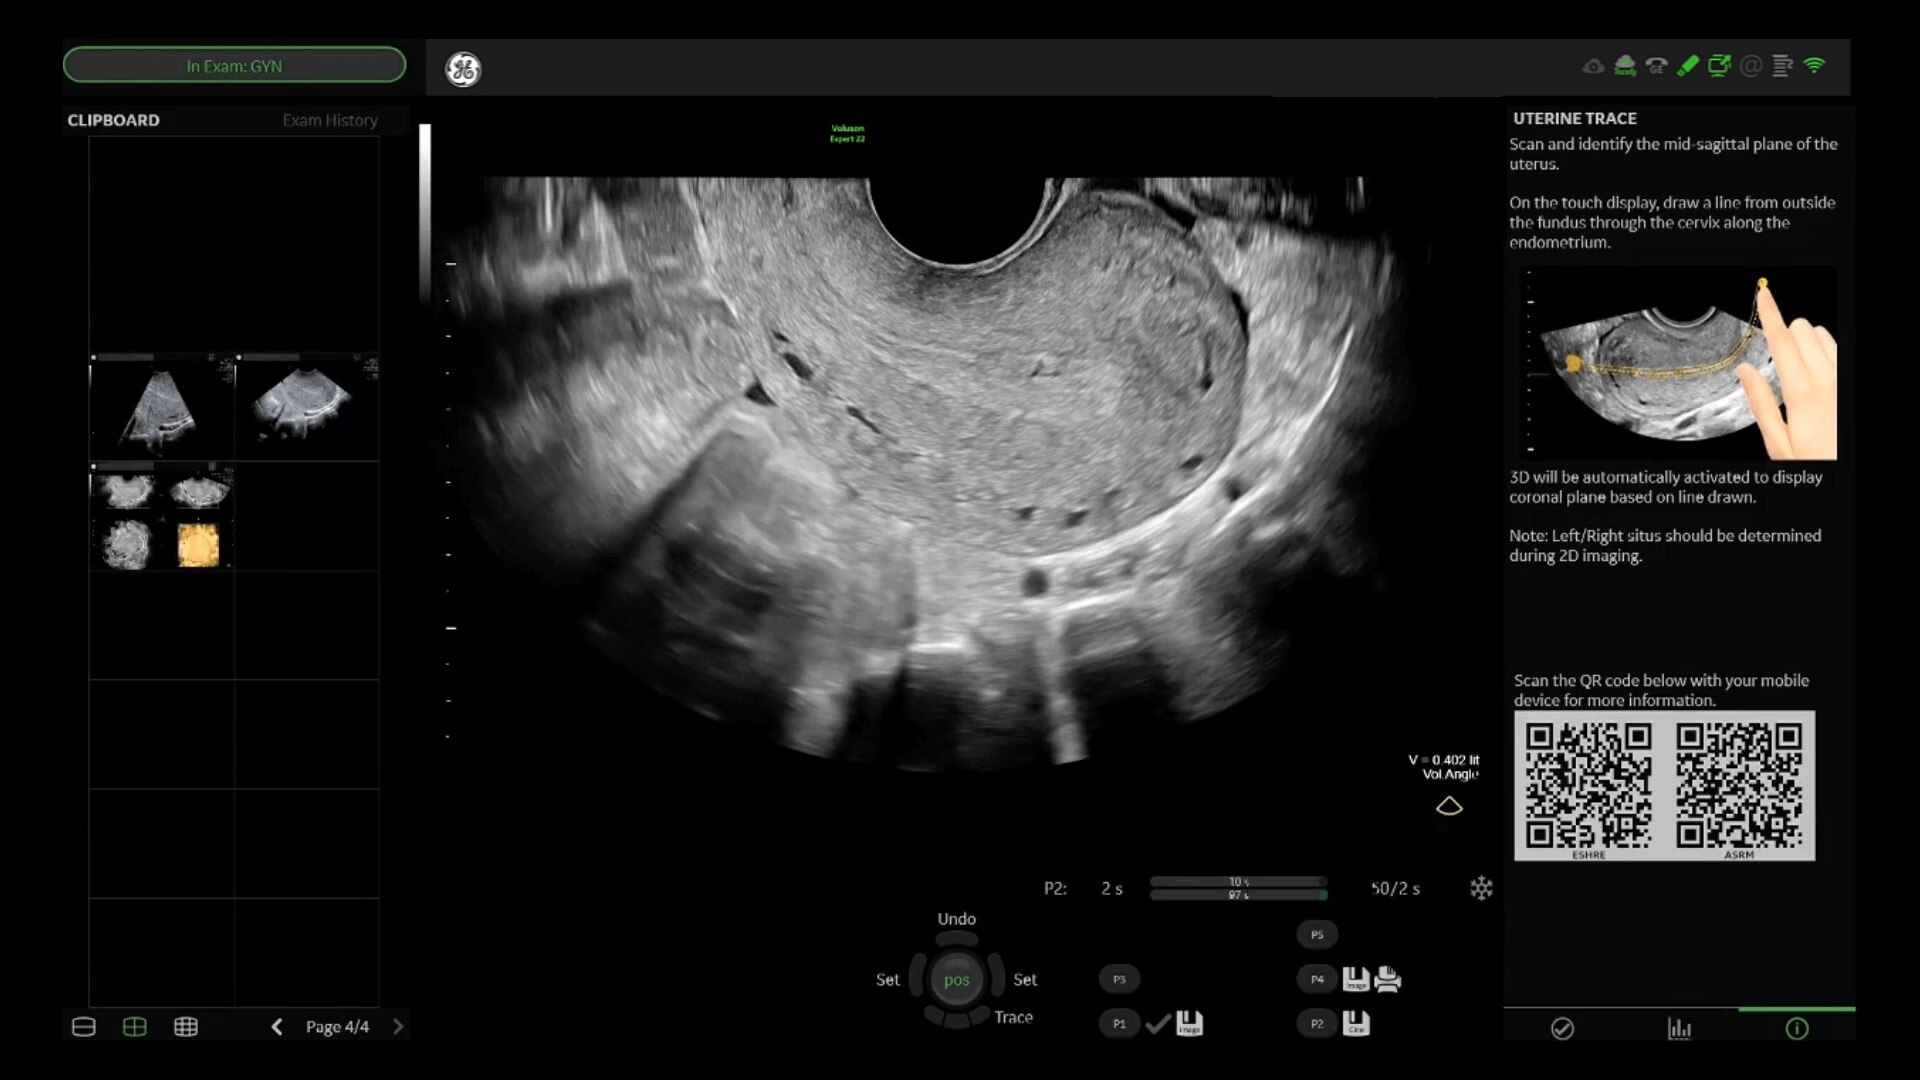

Uterine Trace

Easy display coronal view of uterus.

• Uterine Trace acquires the volume & then displays the coronal view of the uterus to simplify identification & reporting of uterine malformations.

• Easy, accessible 3D for simple, efficient gynecology exams

• Uterine Trace acquires the volume and then displays the coronal view of the uterus linking to ASRM, ESHRE and ESGE Uterine Classification guidelines to simplify identification and reporting of uterine malformations